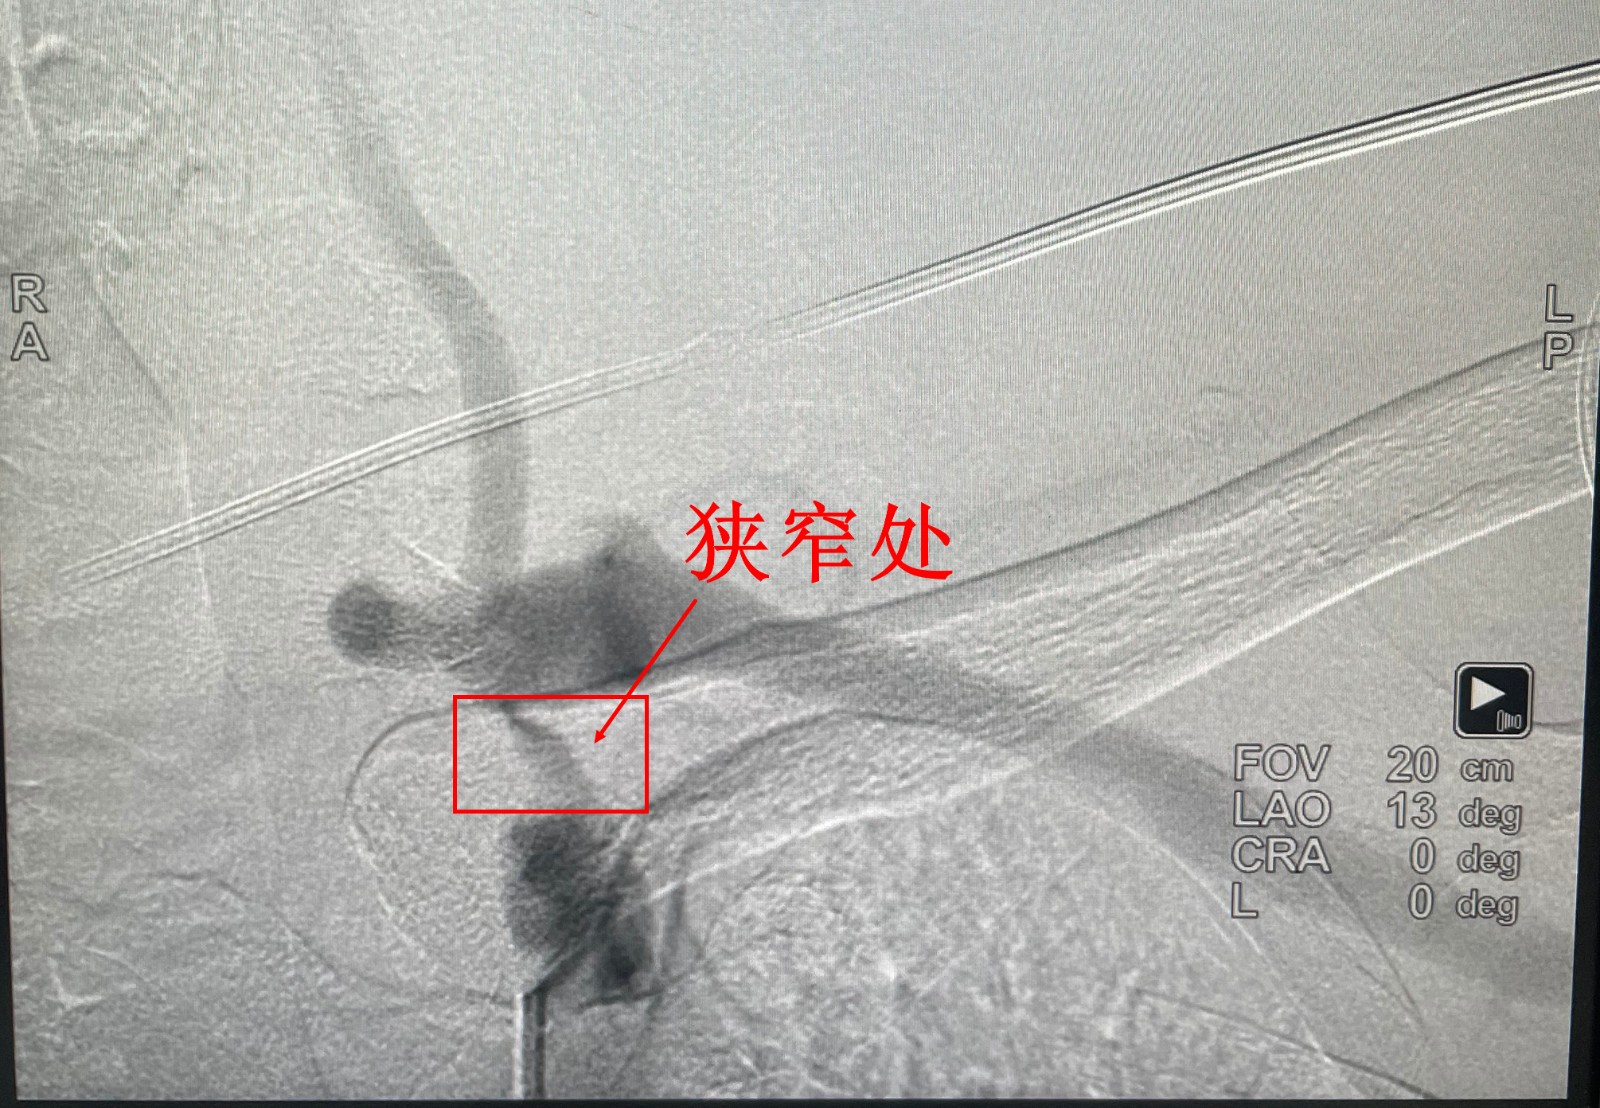

经头颈CTA和脑血管造影检查,结果证实了他的判断:患者左锁骨下动脉起始处狭窄超过90%,右椎动脉纤细,血流缓慢。如不及时处理,随时可能发生永久性脑损伤。

8月29日,在完善各项术前准备后,叶伟团队为患者实施微创介入手术。通过穿刺股动脉,将导管精准送达病变部位,先行球囊扩张狭窄段,再成功植入血管支架。术后造影显示,原本狭窄的血管恢复通畅,“盗血”现象立即消失。